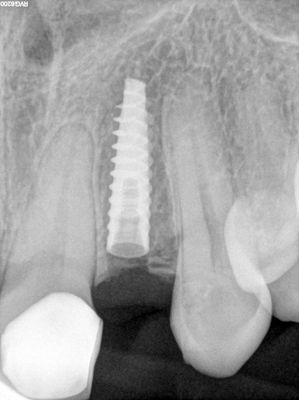

congenitally missing lateral incisors, limited M-D spacing, time taken to position osteotomy, narrow implant placed, loaded with temp crown from lab processed shell. Out of occlusion.